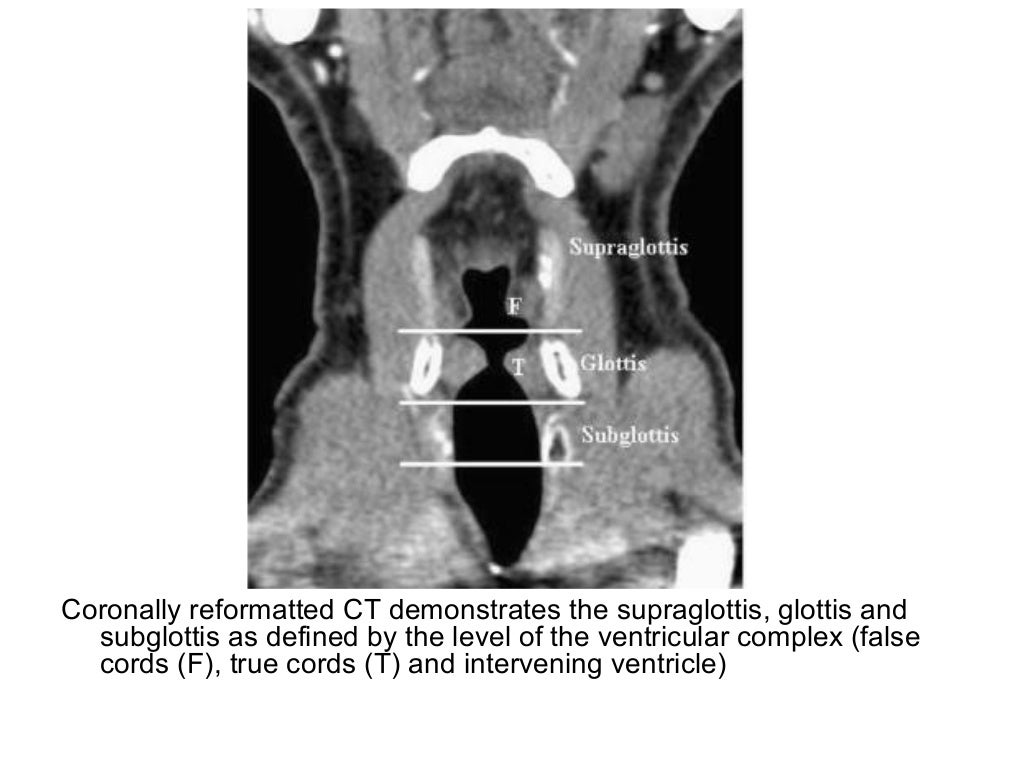

Axial CT slices showing the delineation of the supraglottic larynx (A) (a), glottic area (B) (b Ct Anatomy Of Pharynx Furthermore, the broad range of. During respiration, the pharynx is an active conduit for the passage of air from the nasopharynx to the laryngeal aditus. The pharynx is a hollow muscular tube which extends from the skull base to the inferior border of the cricoid cartilage, and is an integral. Normal nasopharynx on ct and mri. The following article demonstrates. Ct Anatomy Of Pharynx.